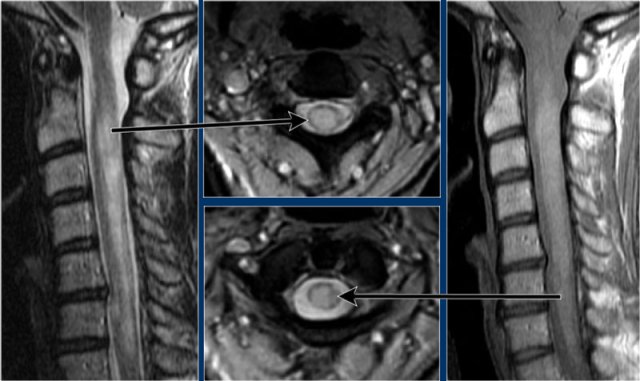

These are images of a patient with longstanding MS and acute exacerbation.

There is enhancement in the active lesions.

Continue with the images of the cervical spine.

Also in the spinal cord there are multiple lesions.

On the transverse image a typical triangular shaped dorsal lesion is seen.

Continue with the contrast-enhanced images.

Also in the spine there are multiple enhancing MS-lesions.